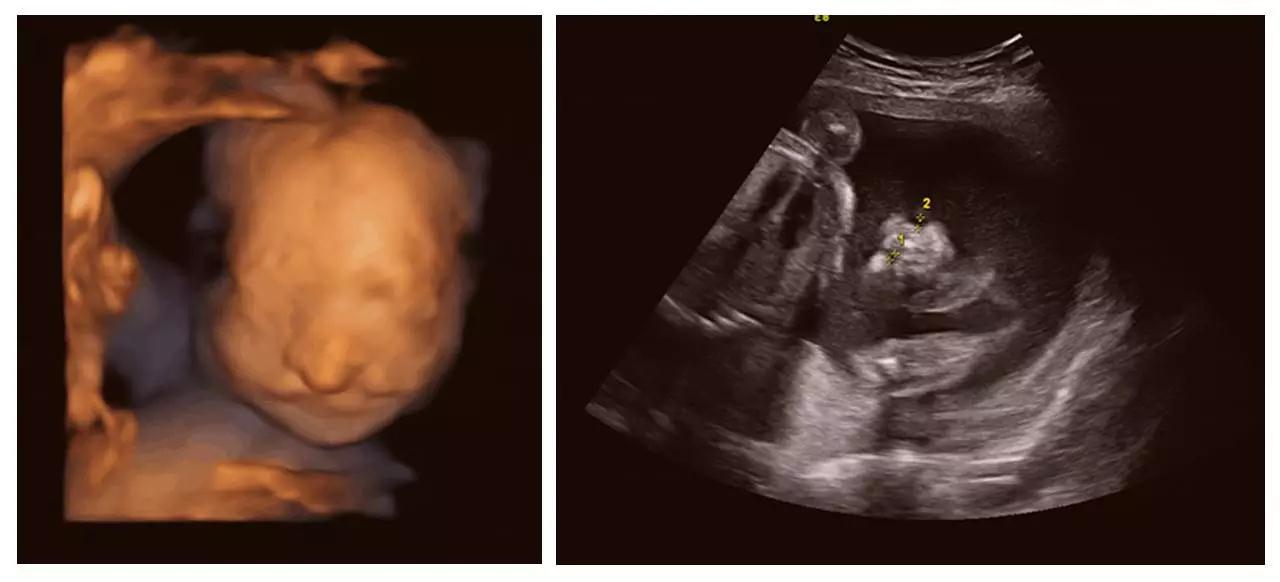

在Carissa怀孕25周的次孕检中,她在四维彩超(四维彩超)视频中发现,自己的个女儿首先亲吻了另个女儿的胸口,然后她们慢慢接近,后竟然相互用嘴亲吻!

看到这相亲相爱的幕,让准妈妈的心都要融化了,她说:“我不知道如何解释这个事情,但是看到她们这么亲近,真是太好了。”小生命真的很神奇,原来她们还没出生就已经学会接吻了。太可爱啦!祝愿这两个萌宝健康地出生!

夫妇俩给两个女儿取名为Isabella和Callie。妈妈Carissa把图像照片上传到了社交网站上。她在其中张照片中写道,Isabella在姐姐Callie的脸颊上印了个吻。在另张照片中,她写道,在这刻她很感恩,迫不及待地想要认识这两位珍贵的公主。

正是通过神奇的四维彩超(四维彩超),我们起见证了这有爱的幕。四维彩超(四维彩超)的出现对于妇产科学界意义重大,在探头下,我们可以清晰地看见宝宝的动态,看见宝宝发育的情况。不仅如此,四维彩超(四维彩超)能通过清晰的画面对胎儿的体表进行检查,及早发现唇裂、脊柱裂,大脑、肾、心脏、骨骼发育不良等各种畸形情况,检测和发现各种异常。简单的说,四维彩超(四维彩超)的作用,就是从零岁起监测宝宝的发育情况,保障每个新生儿的健康!

济南艾玛妇产医院作为山东首家 JCI 金牌妇产专科医院,在今年年初,又顺利成为济南市基本医疗保险定点医疗单位,集医疗安全和客户就诊的便捷度于体。济南艾玛妇产医院直非常重视围产期保健及宝宝出生缺陷的预防,率先引进美GE-E8高清四维彩超(四维彩超)设备,从0岁开始守护宝宝的健康,见证宝宝的成长。